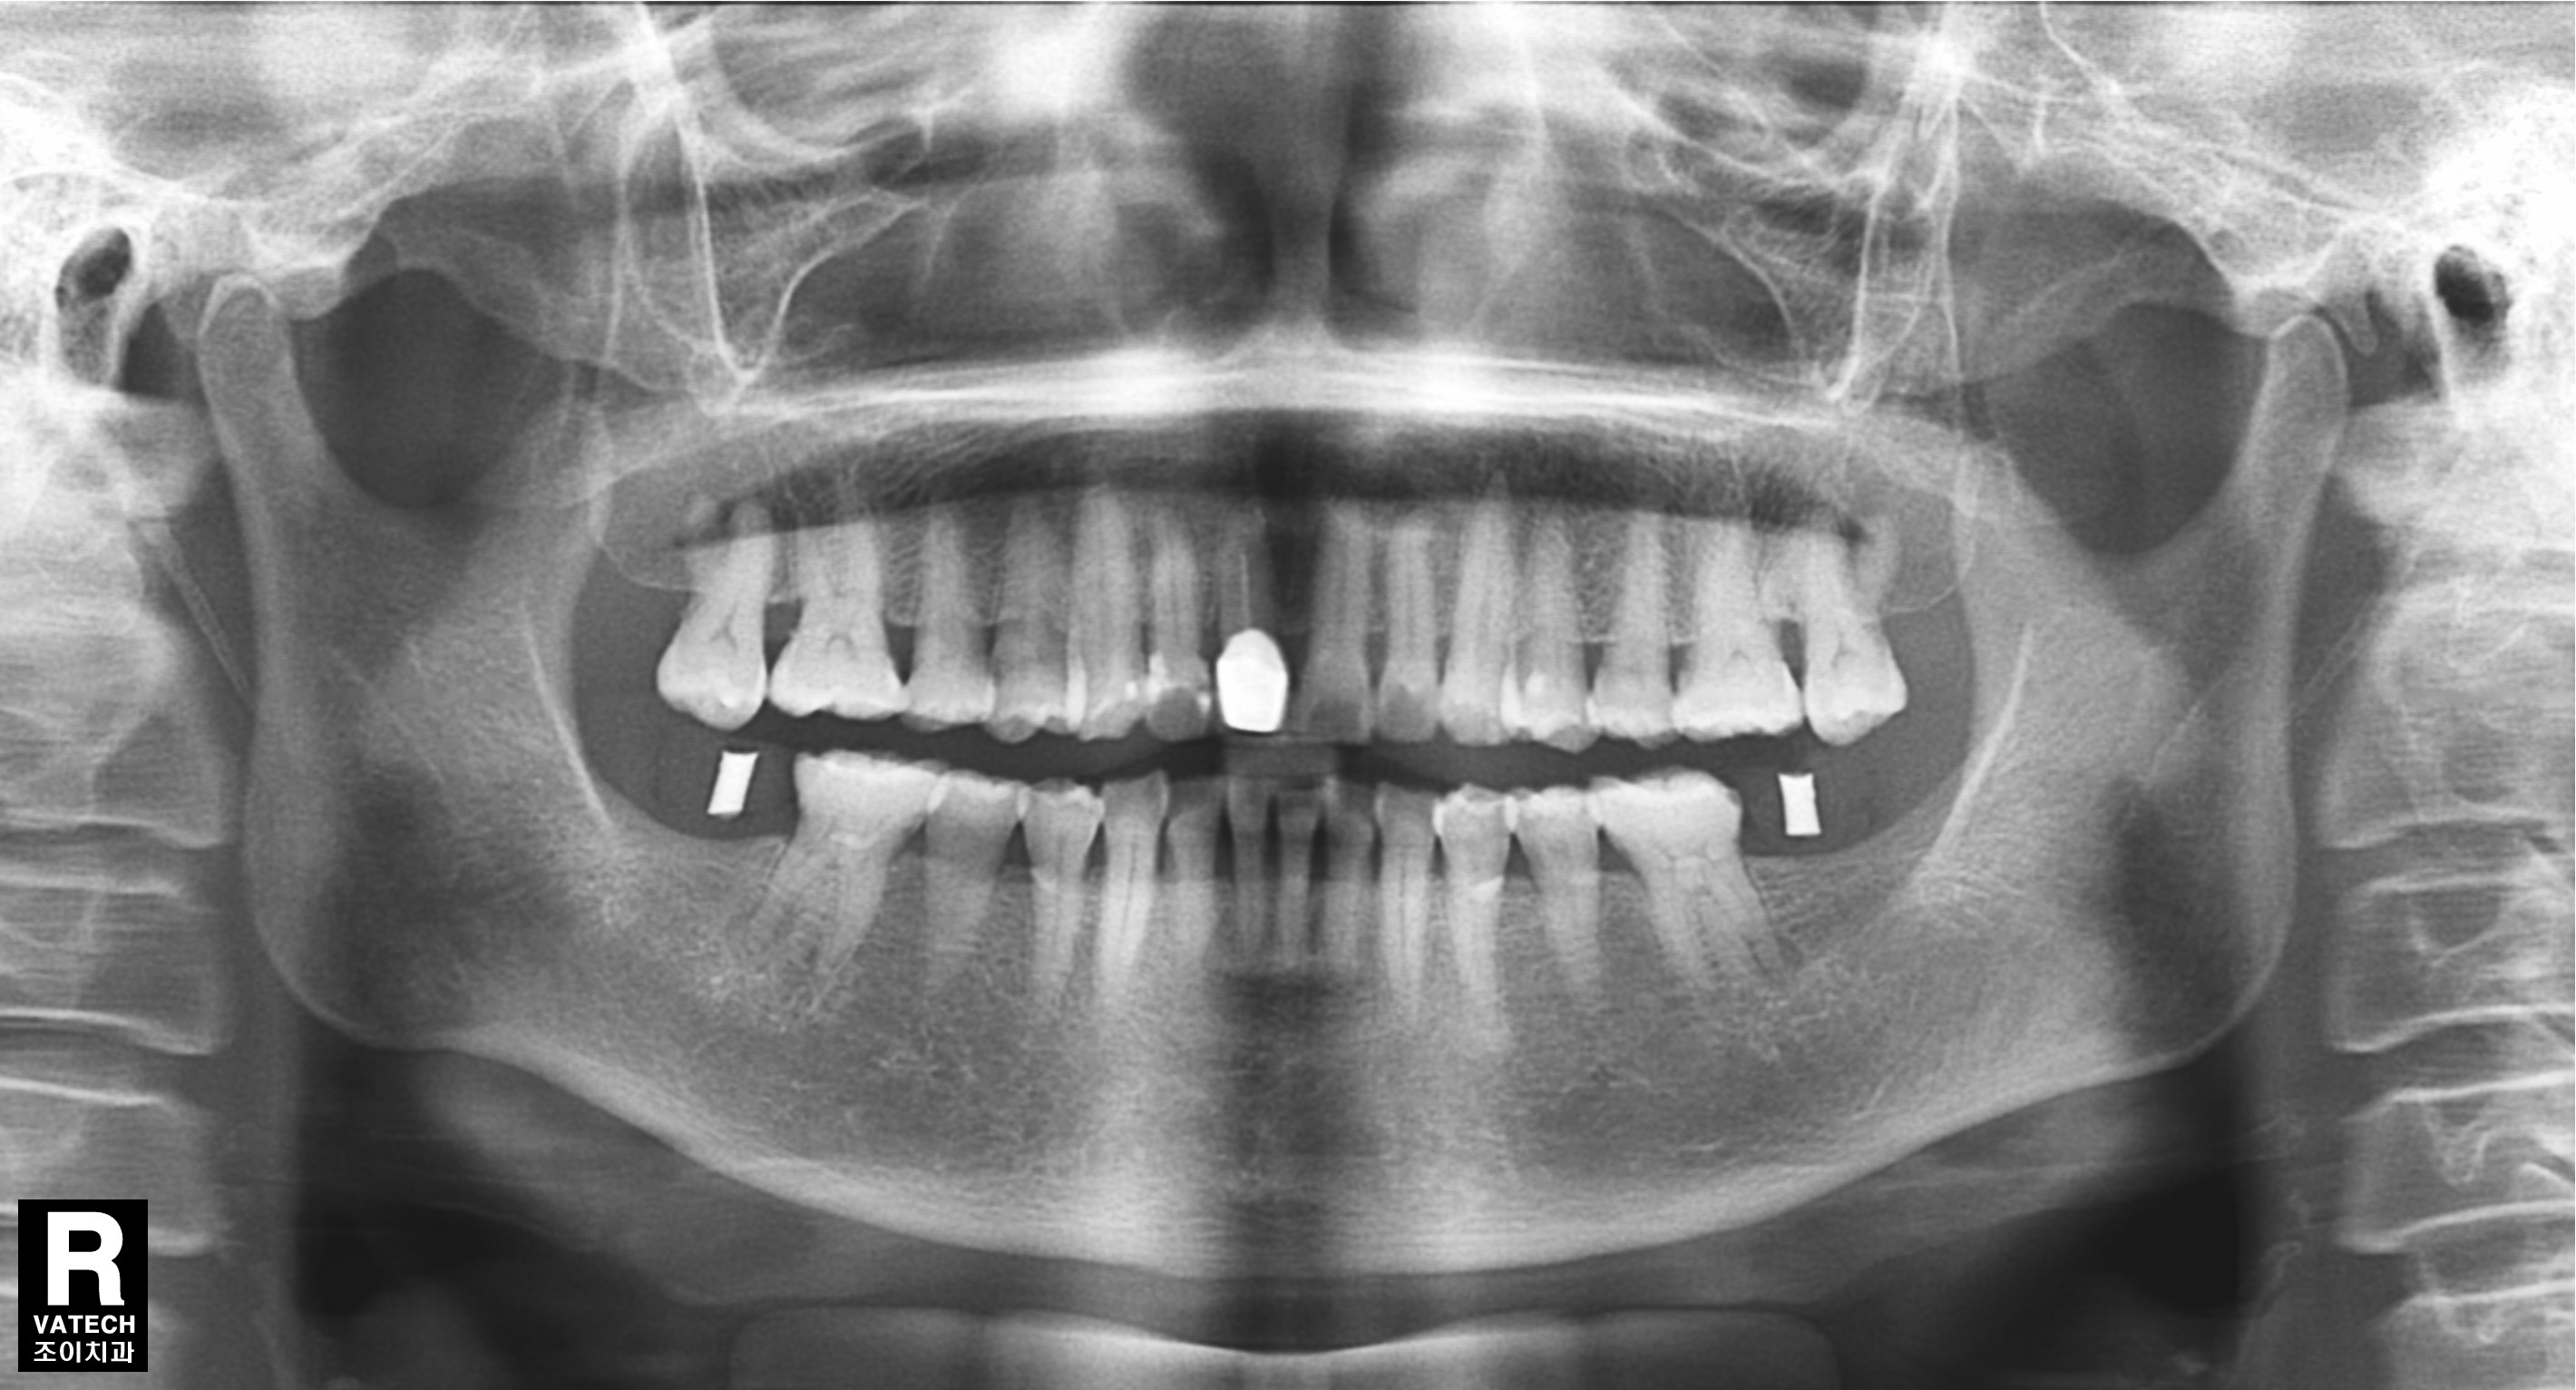

장시간 노출된 강한 교합으로 후방구치가 상실되고 그 앞니조차 뿌리에 염증이 생겨 통증이 있는 경우입니다.

상실된 치아는 임플란트로 수복하고, 염증이 생긴 치아는 근관치료와 보철치료로 수복한 증례입니다.